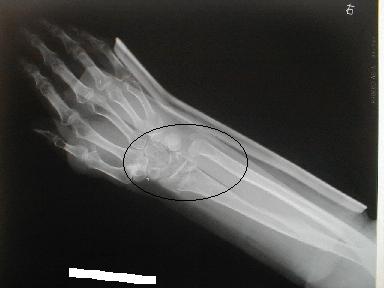

1月21日受傷 正面像

とう骨下端 尺骨茎状突起骨折

側面像